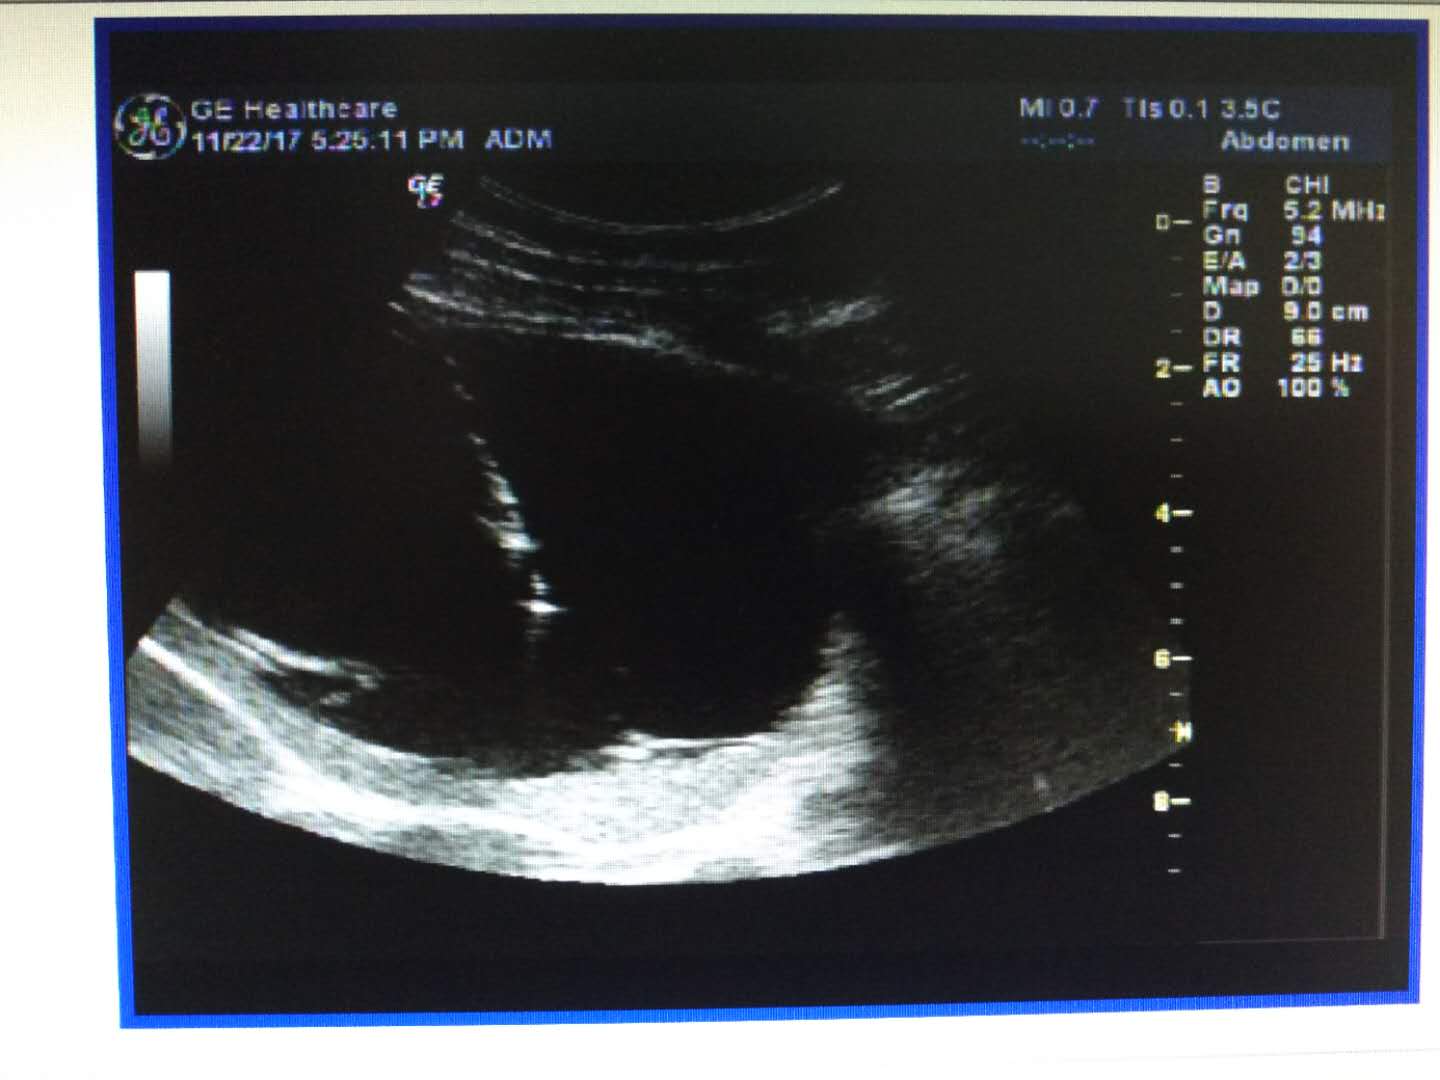

患者张某,男性,23岁,体检发现脾脏占位直径约10cm,在上海中山医院CT确诊巨大脾囊肿,建议手术。由于脾脏具有实质较脆、血流丰富的组织学特点, 脾脏的囊性占位病变传统治疗方法多采取脾脏切除手术,考虑到患者年纪轻,如切除脾脏,较为可惜,超声科和普外科本着“一切为了病患”服务理念,结合患者身体实际情况,决定在超声引导下为该患者实施脾囊肿的穿刺置管引流+硬化术,经过精心的术前准备,术中仔细准确操作,最终顺利抽出囊液,囊肿得以消除,保留了脾脏。

巨大脾囊肿

脾囊肿穿刺置管

脾囊肿抽出的囊液